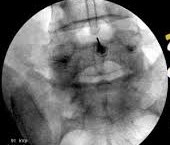

Η ουραία επισκληρίδιος έγχυση είναι η χορήγηση κορτιζόνης και τοπικού αναισθητικού μέσω του ιερού τρήματος που αποτελεί το κατώτερο τμήμα της σπονδυλικής στήλης. Μέσω του τρήματος μπορεί να γίνει μεμονωμένη έγχυση ουσιών ή να εισαχθεί επισκληρίδιος καθετήρας που θα κάνει συγχρόνως και λύση τυχόν συμφύσεων σε περιπτώσεις μετεγχειρητικού άλγους.